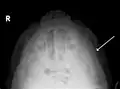

Fracture of the zygomatic arch as seen on plain X-ray -